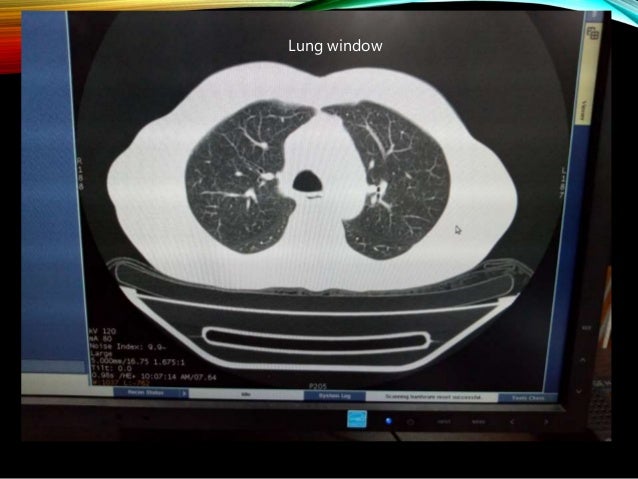

Ct Numbers Window Width And Window Level